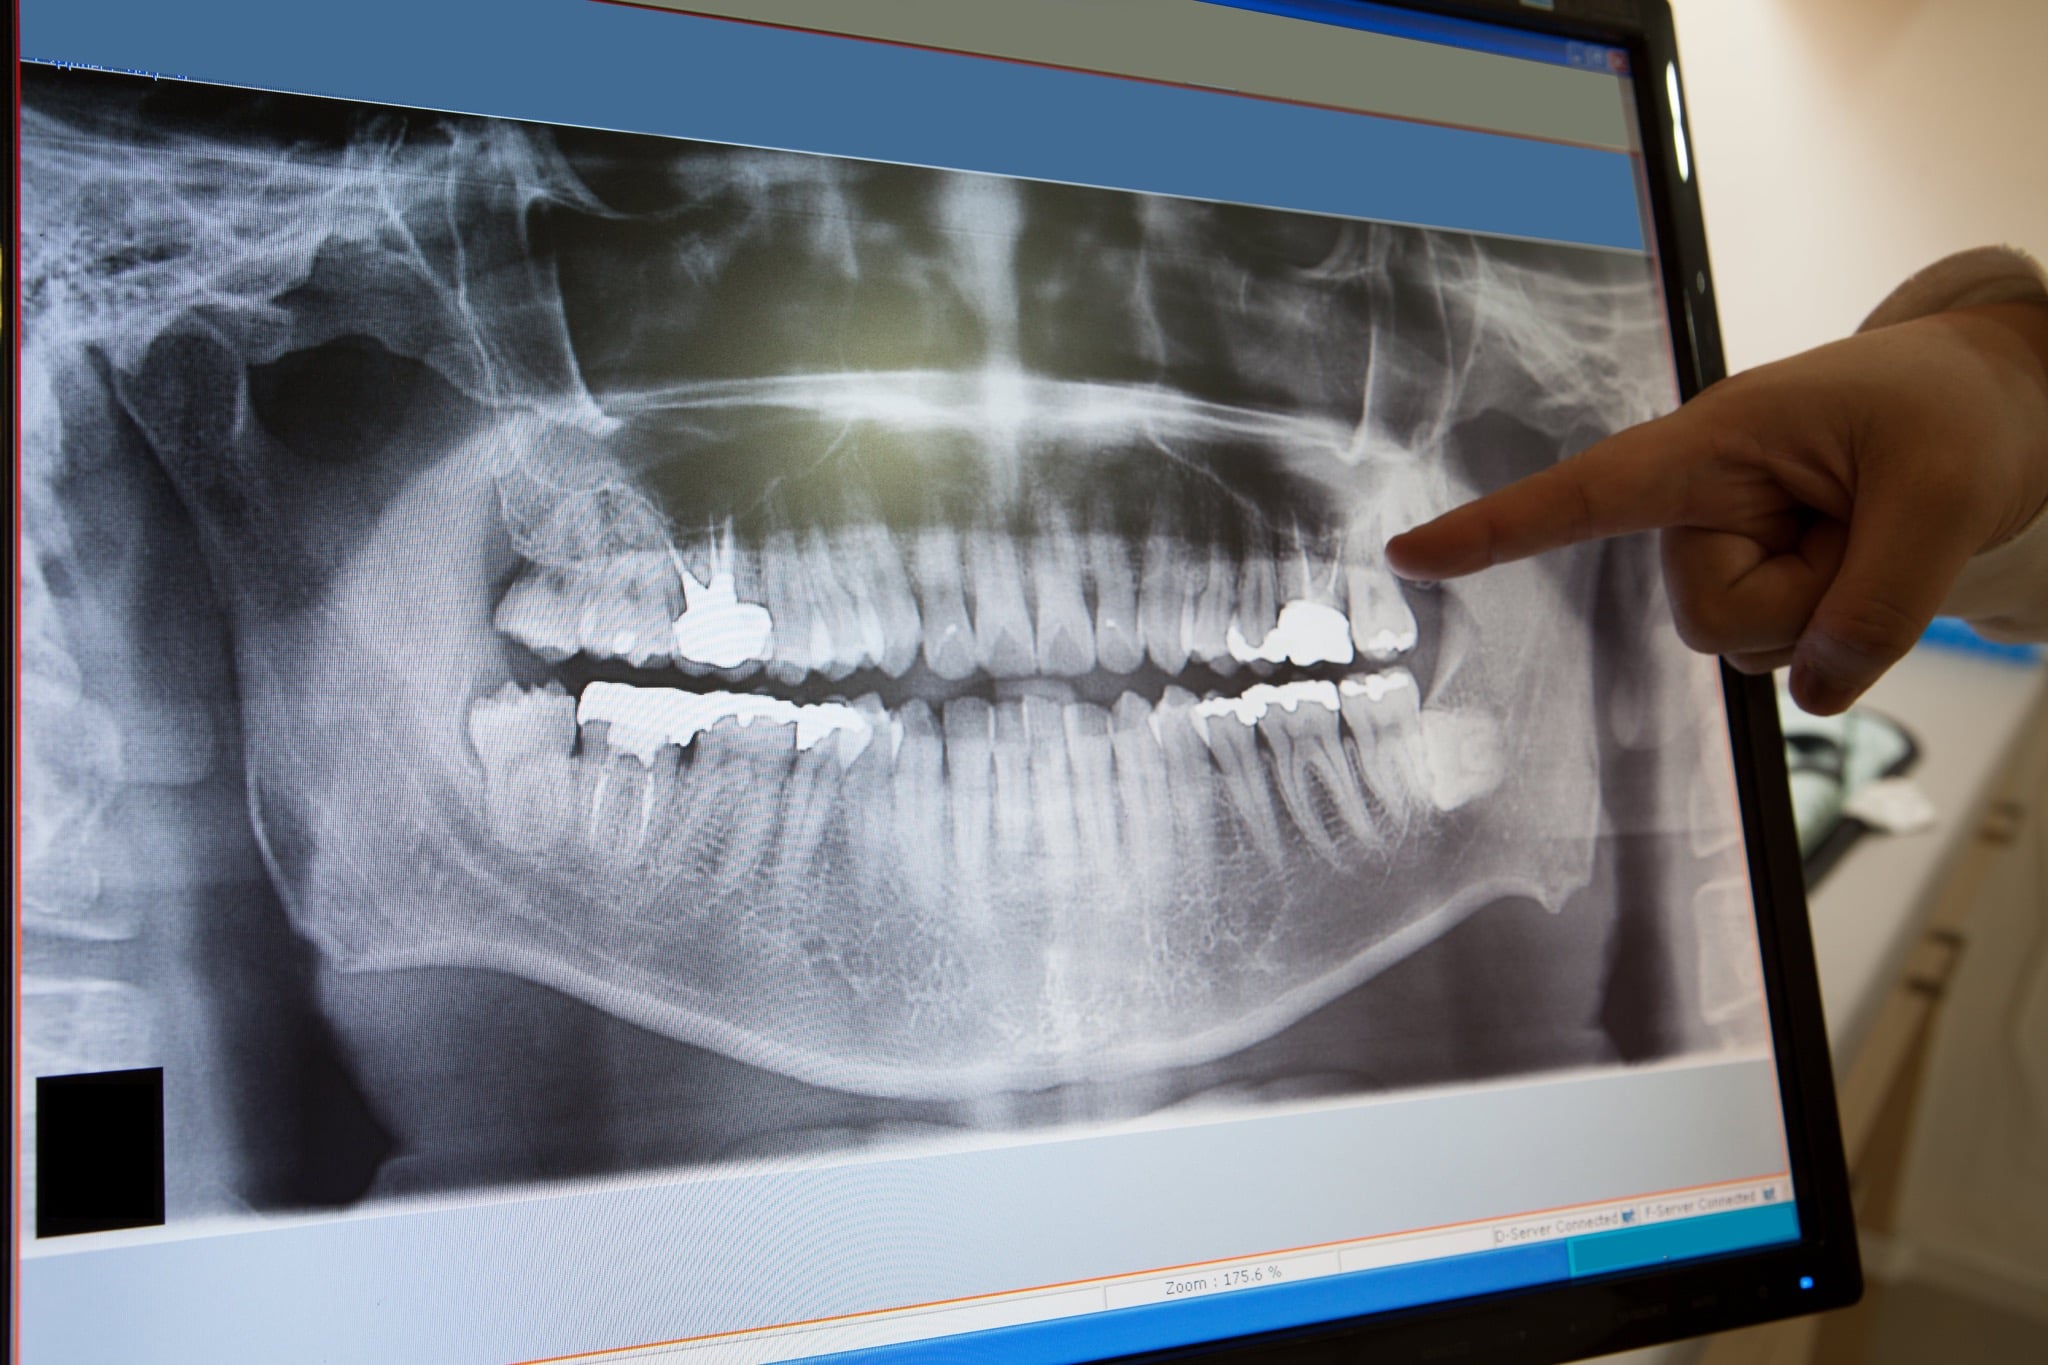

Het eerste consult neemt ongeveer 15 tot 30 minuten in beslag. We controleren uw gegevens, onderzoeken uw gebit en maken röntgenfoto’s. Op basis hiervan bespreken wij samen met u diverse behandelmethoden. Vervolgens maken we een afspraak voor de behandeling.

- Een wortelkanaalbehandeling duurt gemiddeld zo’n anderhalf tot twee uur per tand of kies. Van tevoren willen we eerst graag een consult uitvoeren, deze duurt ongeveer 15 tot 20 minuten. Hierbij controleren we uw gegevens, onderzoeken we uw gebit en maken röntgenfoto’s. Ongeveer een jaar na de wortelkanaalbehandeling wordt u opgeroepen voor een controle. We kijken dan of het wortelkanaal helemaal vrij is van ontstekingen.